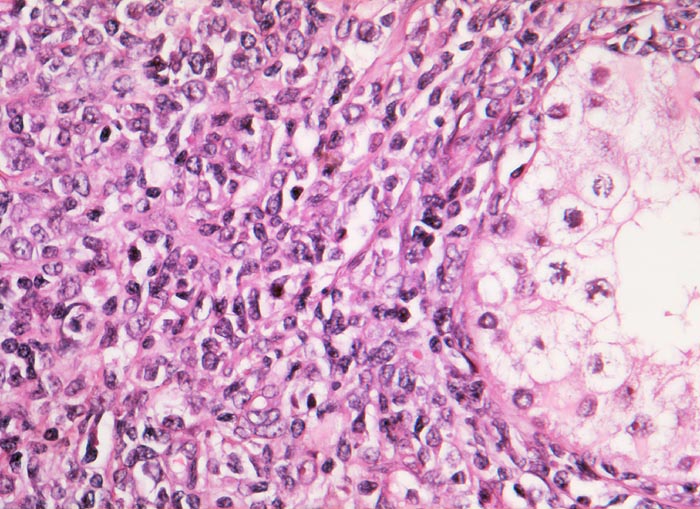

PathoPic – image database / PathoPic ID 3094 - Diffuses grosszelliges B-Zell Lymphom

Diffuses grosszelliges B-Zell Lymphom

Hoden

Rechts im Bild der Anschnitt eines erhaltenen Hodentubulus. Im Interstitium ein diffuses Infiltrat von mittelgrossen bis grossen Lymphomzellen mit grossen blasigen Kernen und teilweise prominenten Nukleolen.

Die Abgrenzung eines Seminoms oder embryonalen Karzinoms von einem hämatologischen Tumor kann schwierig sein, wenn man nicht daran denkt. Bei älteren Männern sind Keimzelltumoren abgesehen vom spermatozytischen Seminom sehr selten.